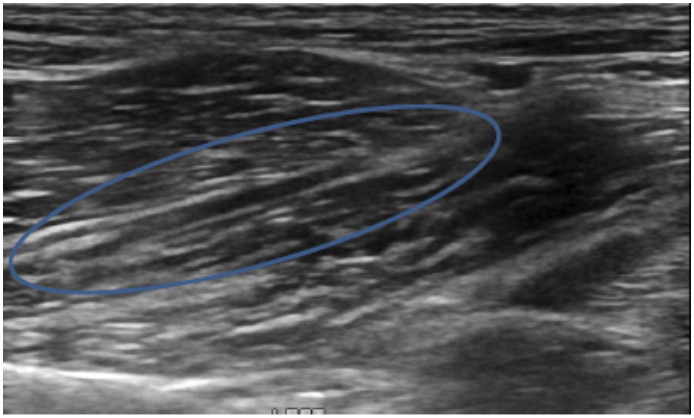

Objective: Iliopsoas injury and strain is a commonly diagnosed disease process, especially amongst working and sporting canines. There has been very little published literature regarding iliopsoas injuries and there is no information regarding the ultrasound evaluation of abnormal iliopsoas muscles. This manuscript is intended to describe the ultrasound findings in 73 canine agility athletes who had physical examination findings consistent with iliopsoas discomfort. The population was chosen given the high incidence of these animals for the development of iliopsoas injury; likely due to repetitive stress.

Methods: Medical records of 73 agility performance canines that underwent musculoskeletal ultrasound evaluation of bilateral iliopsoas muscle groups were retrospectively reviewed. Data included signalment, previous radiographic findings, and ultrasound findings. A 3-tier grading scheme for acute strains was used while the practitioner also evaluated for evidence of chronic injury and bursitis.

Results: The majority of pathologies were localised to the tendon of insertion, with the majority being low grade I-II strains (80.8%). Tendon fibre disruption (71.2%) and indistinct hypoechoic lesions (91.8%) were the most common of acute changes noted. Hyperechoic chronic changes were noted in 84.9 percent of cases. Acute and chronic changes were commonly seen together (62.8%).

Conclusion: Diagnostic musculoskeletal ultrasound was used to identify lesions of the iliopsoas tendon consistent with acute and chronic injury, as well as identifying the region of pathology. The majority of agility performance dogs had low grade acute strains based on the tiered system, with mixed acute and chronic lesions being noted frequently.

Application: Diagnostic musculoskeletal ultrasound provides a non-invasive diagnostic modality for patients suspected of having an iliopsoas strain.